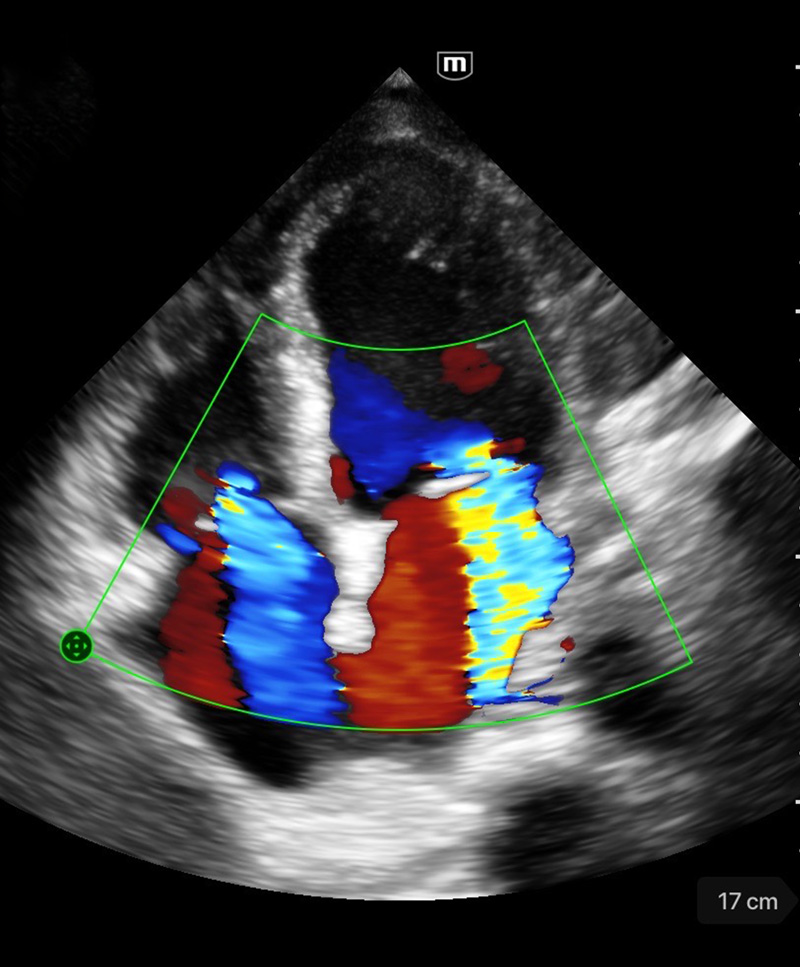

Clinical Images

Dilated Cardiomyopathy

Clinical Images

Dilated Cardiomyopathy